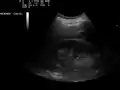

A normal ultrasonographic view of Morison's pouch. The bright line is the capsule of the kidney; there is no fluid present and hence no visible space.